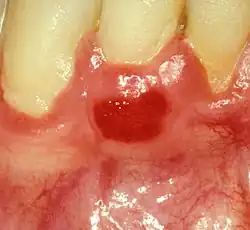

Plasma cell gingivitis in an adult (histologically verified).

Plasma cell gingivitis appears as mild gingival enlargement and may extend from the free marginal gingiva on to the attached gingiva.[6] Sometimes it is blended with a marginal, plaque induced gingivitis, or it does not involve the free marginal gingiva. It may also be found as a solitude red area within the attached gingiva (pictures). In some cases the healing of a plaque-induced gingivitis or a periodontitis resolves a plasma cell gingivitis situated a few mm from the earlier plaque-infected marginal gingiva. In case of one or few solitary areas of plasma cell gingivitis, no symptoms are reported from the patient. Most often solitary entities are therefore found by the dentist.[2]

The gums are red, friable, or sometimes granular, and sometimes bleed easily if traumatised.[6] The normal stippling is lost.[7] There is not usually any loss of periodontal attachment.[6] In a few cases a sore mouth can develop, and if so pain is sometimes made worse by toothpastes, or hot or spicy food.[7] The lesions can extend to involve the palate.[7]